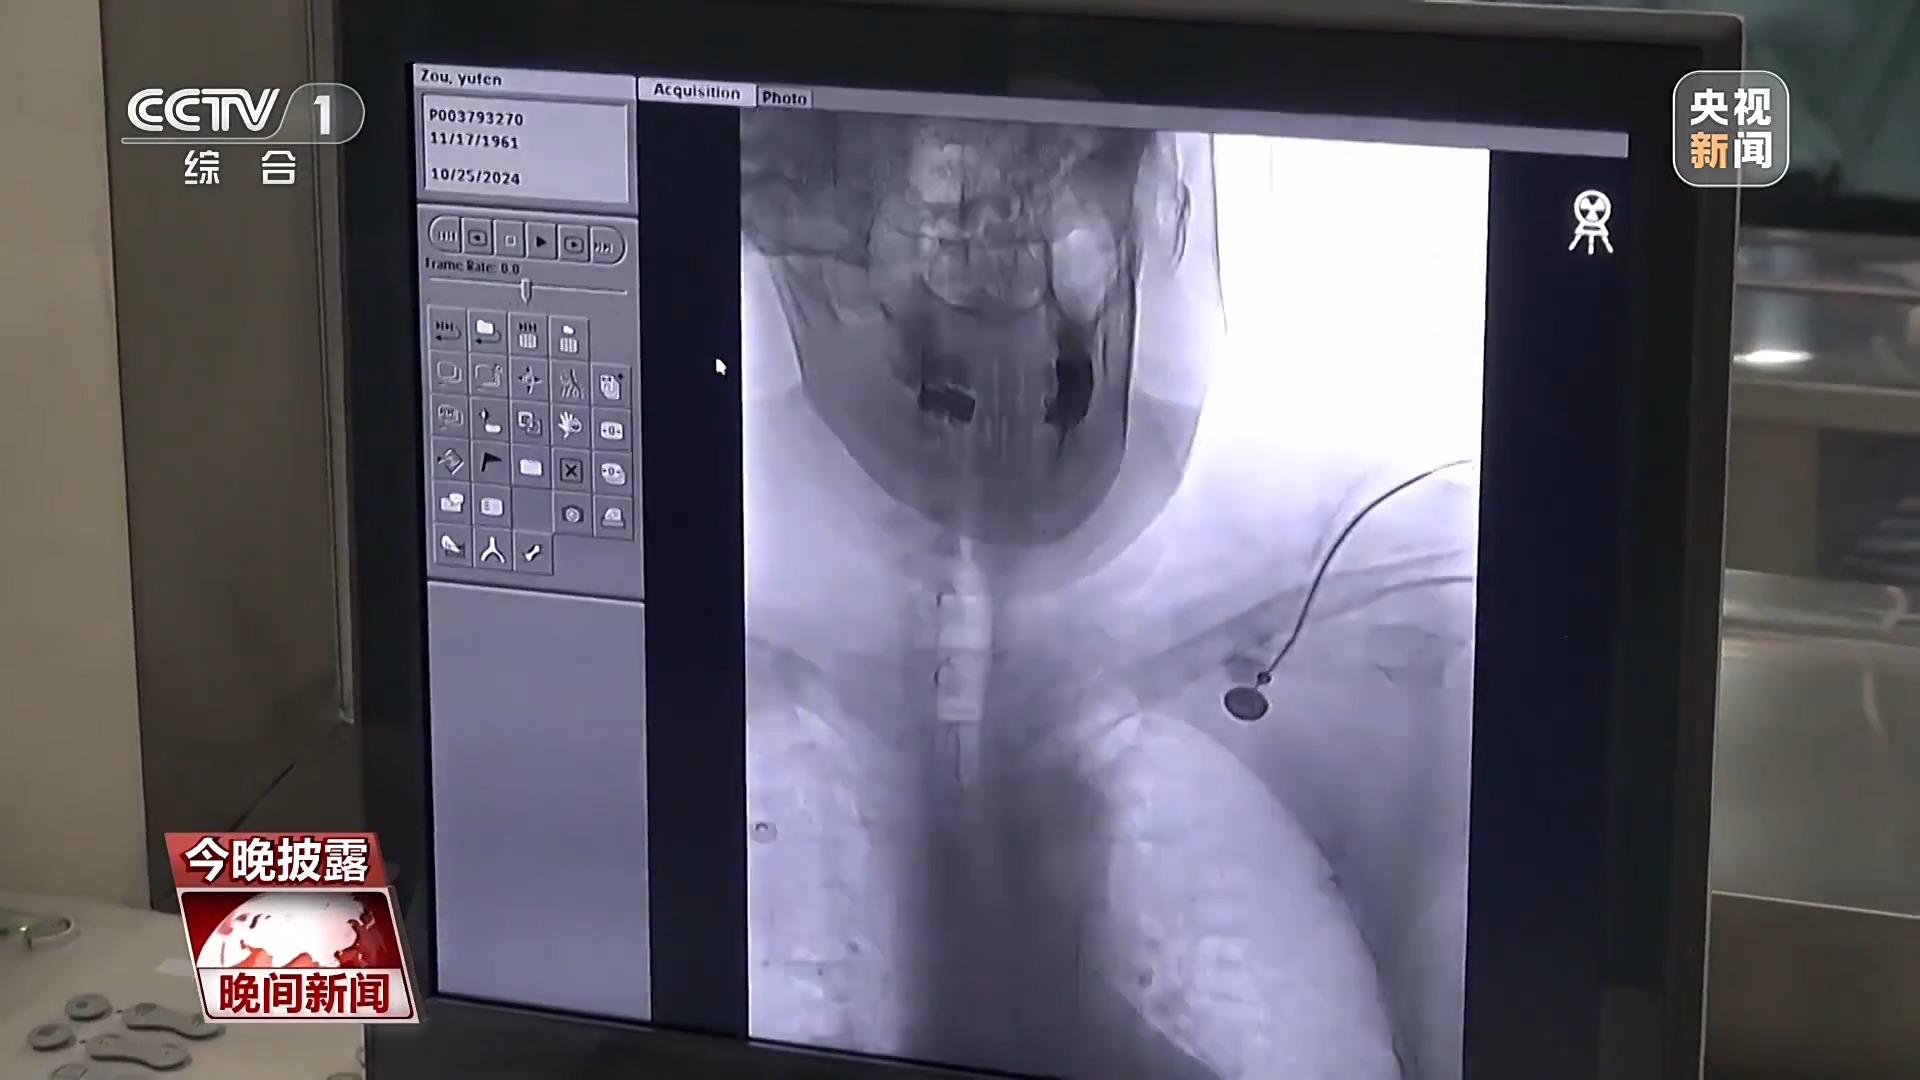

在重庆医科大学附属第一医院,我们见到了刚刚被120送过来44岁的脑卒中患者邹女士。邹女士也是因为突然出现右侧肢体无力和言语不清等症状,被紧急送往医院。

重庆医科大学附属第一医院神经内科主任医师 胡子成:我们先安排造影,它是一个更加精细的检查,可以看里面血管的狭窄程度到底有多大,它的带长怎么样。造影之后,再说下一步要不要处理。

经过详细的检查和评估,医生决定为患者进行脑血管介入手术。手术过程中,医生使用了先进的导丝和微导管技术,成功开通了患者闭塞的血管。